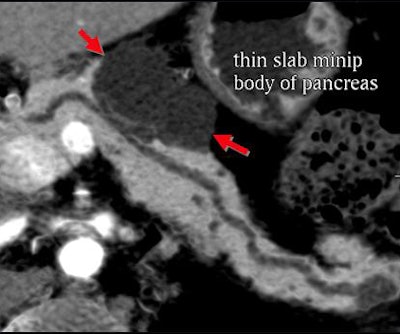

Certainly imaging-based diagnosis of the cysts has its limitations. For one thing, MDCT can diagnose six different pancreatic lesion types, including side branch intraductal papillary mucinous neoplasms (IPMNs), serous microcystic adenomas, epithelial cysts, mucinous cystic neoplasms, lymphatic cysts, and cystic islet cell tumors. But it can't always tell them apart.

Worrisome features for malignancy are solid tissue within the cyst, obstruction of the main pancreatic duct ≥ 1 cm or the common bile duct, regional lymphadenopathy, or interval enlargement of a lesion, Jeffrey said.

Small cystic lesions not worrisome for malignancy under 3 cm include side branch IPMNs, and serous microcystic adenomas, which are easily characterized by their honeycomb matrix that is also easily seen on ultrasound, Jeffrey said.